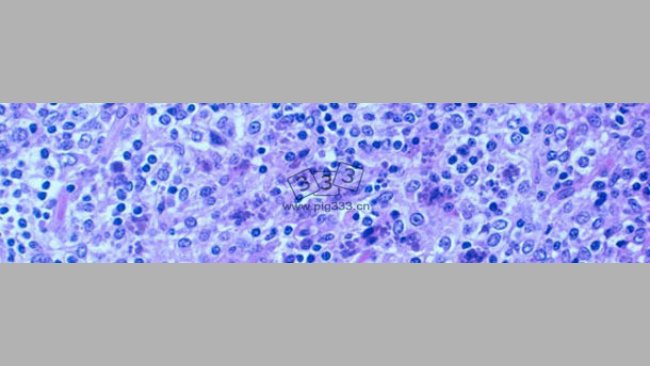

PCV2在发病和健康猪群中感染率都很高,因此利用血清学方法进行该病原的诊断受到质疑。众所周知,环状病毒的诊断必须以Sorden标准为基础。然而,基于试验的种类、可获得性、实验条件以及实验目的,血清学试验具有一定的诊断意义。